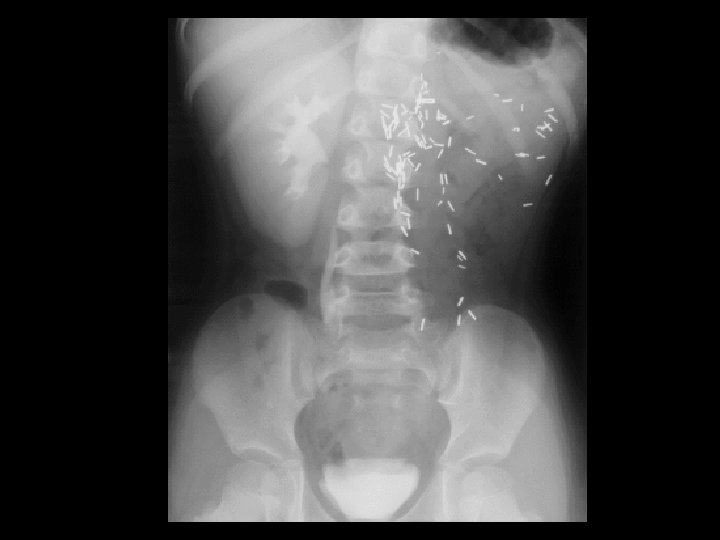

Calcinosis cutis • Findings: – Bone scan shows diffuse activity along the posterior and lateral soft tissues of the buttocks and upper thighs – Normal calcium levels • ddx: – Scleroderma – Dermatamyositis – Polymyositis – SLE – Electrical burns – Idiopathic calcinosis universalis